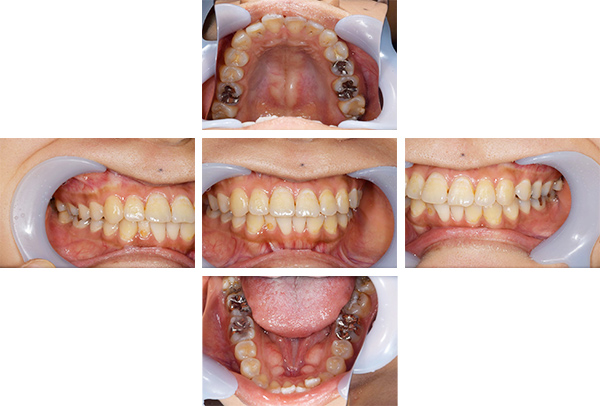

インレー症例

治療前

治療後

治療期間 4回(1ヶ月)

費用 ・セラミックインレー10本

合計:550,000円

治療リスク・副作用 ・詰め物、被せ物をする時は自分の歯を削ることになります

・歯ぎしり・食いしばりが強い方は、セラミックが割れてしまうことがあります。